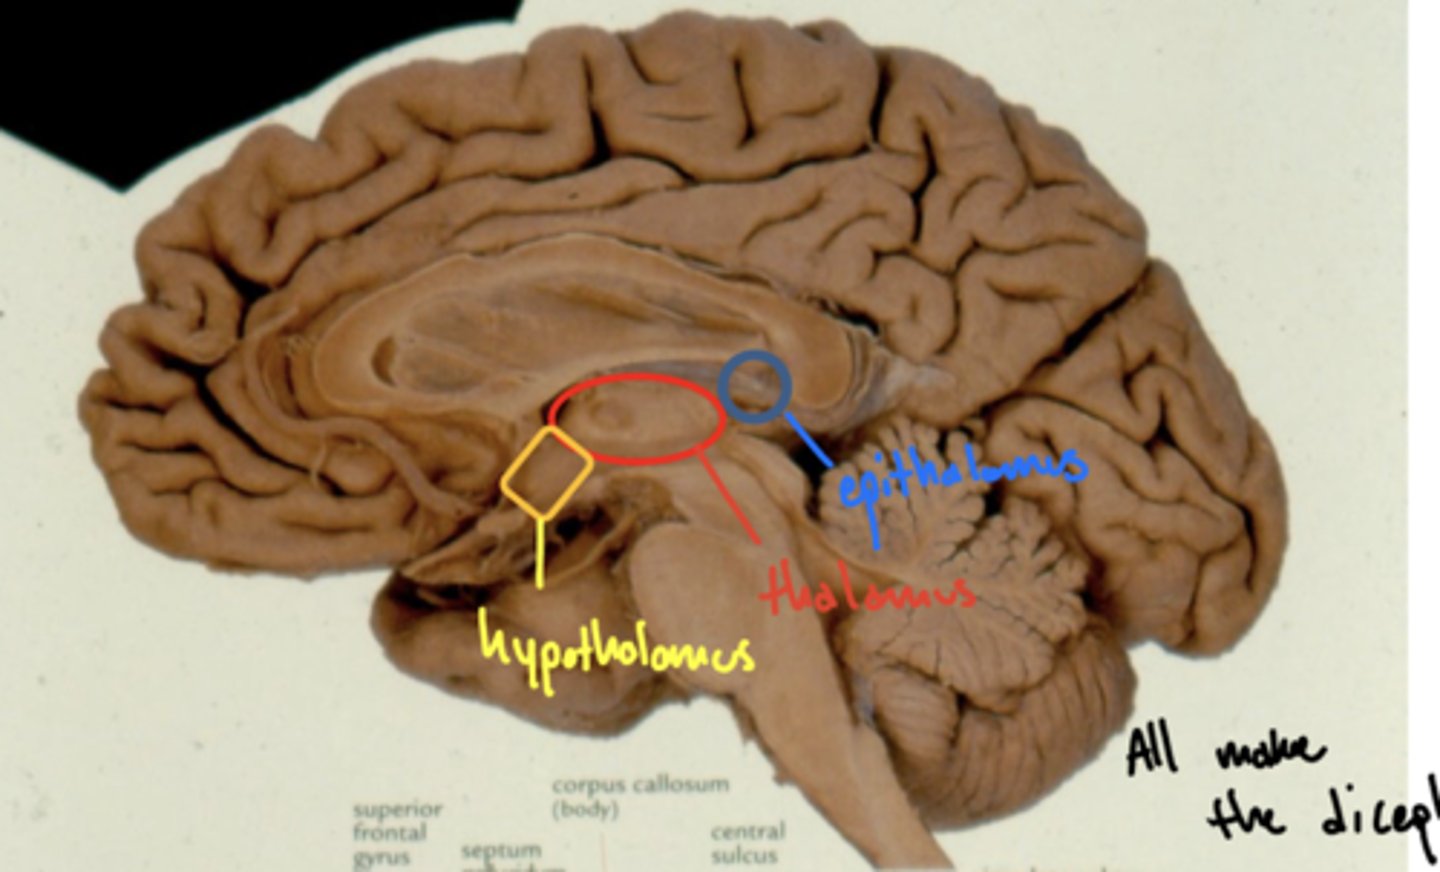

What structures are within the diencephalon?

1. epithalamus

2. thalamus

3. hypothalamus

Where is the hypothalamus in relation to the thalamus?

anteroinferior (in front and below)

Where is the epithalamus in relation to the thalamus?

posterosuperior (behind and above)